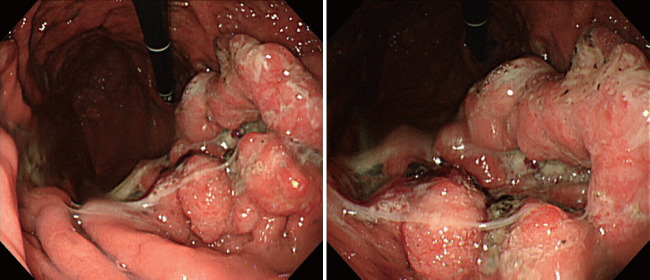

胃腺癌伴肠母细胞分化(GAED)是罕见的,其临床病理特征没有很好的文献记载。然而,报告表明它表现出比传统胃腺癌更具侵袭性的特征,包括淋巴结转移或肝转移。在此,我们报告一例GAED的快速复发和疾病进展。一名55岁男性,被诊断为胃癌(GC),最初的内镜检查结果提示胃癌晚期。由于没有淋巴结或远处转移的证据,他接受了根治性切除。本病为早期胃癌,局限于粘膜下层,最终病理结果无淋巴结转移的证据。然而,手术后6个月,腹部计算机断层扫描发现多发肝转移;病理结果与胃癌转移一致。原发癌病理标本的免疫组化结果显示甲胎蛋白和sal样蛋白4阳性,提示肠母细胞分化,这被认为与快速复发和疾病进展有关。

Gastric adenocarcinoma with enteroblastic differentiation (GAED) is rare and its clinicopathological characteristics are not well documented. However, reports indicate that it exhibits more aggressive characteristics, including lymph node metastasis or liver metastasis, than a conventional gastric adenocarcinoma. Herein, we report a case of GAED with rapid recurrence and disease progression. A 55-year-old male, diagnosed with gastric cancer (GC), demonstrated initial endoscopic findings suggestive of advanced GC. He underwent curative resection since there was no evidence of lymph node or distant metastases. The disease was reported as an early GC that was confined to the submucosal layer, without evidence of lymph node metastasis in the final pathological results. However, six months after surgery, multiple hepatic metastases were found during abdominal computed tomography; the pathological results were consistent with metastasis from the GC. Immunohistochemistry of the primary carcinoma pathological specimens showed positive results for alpha-fetoprotein and sal-like protein 4, suggesting enteroblastic differentiation, which is thought to be associated with rapid recurrence and disease progression.